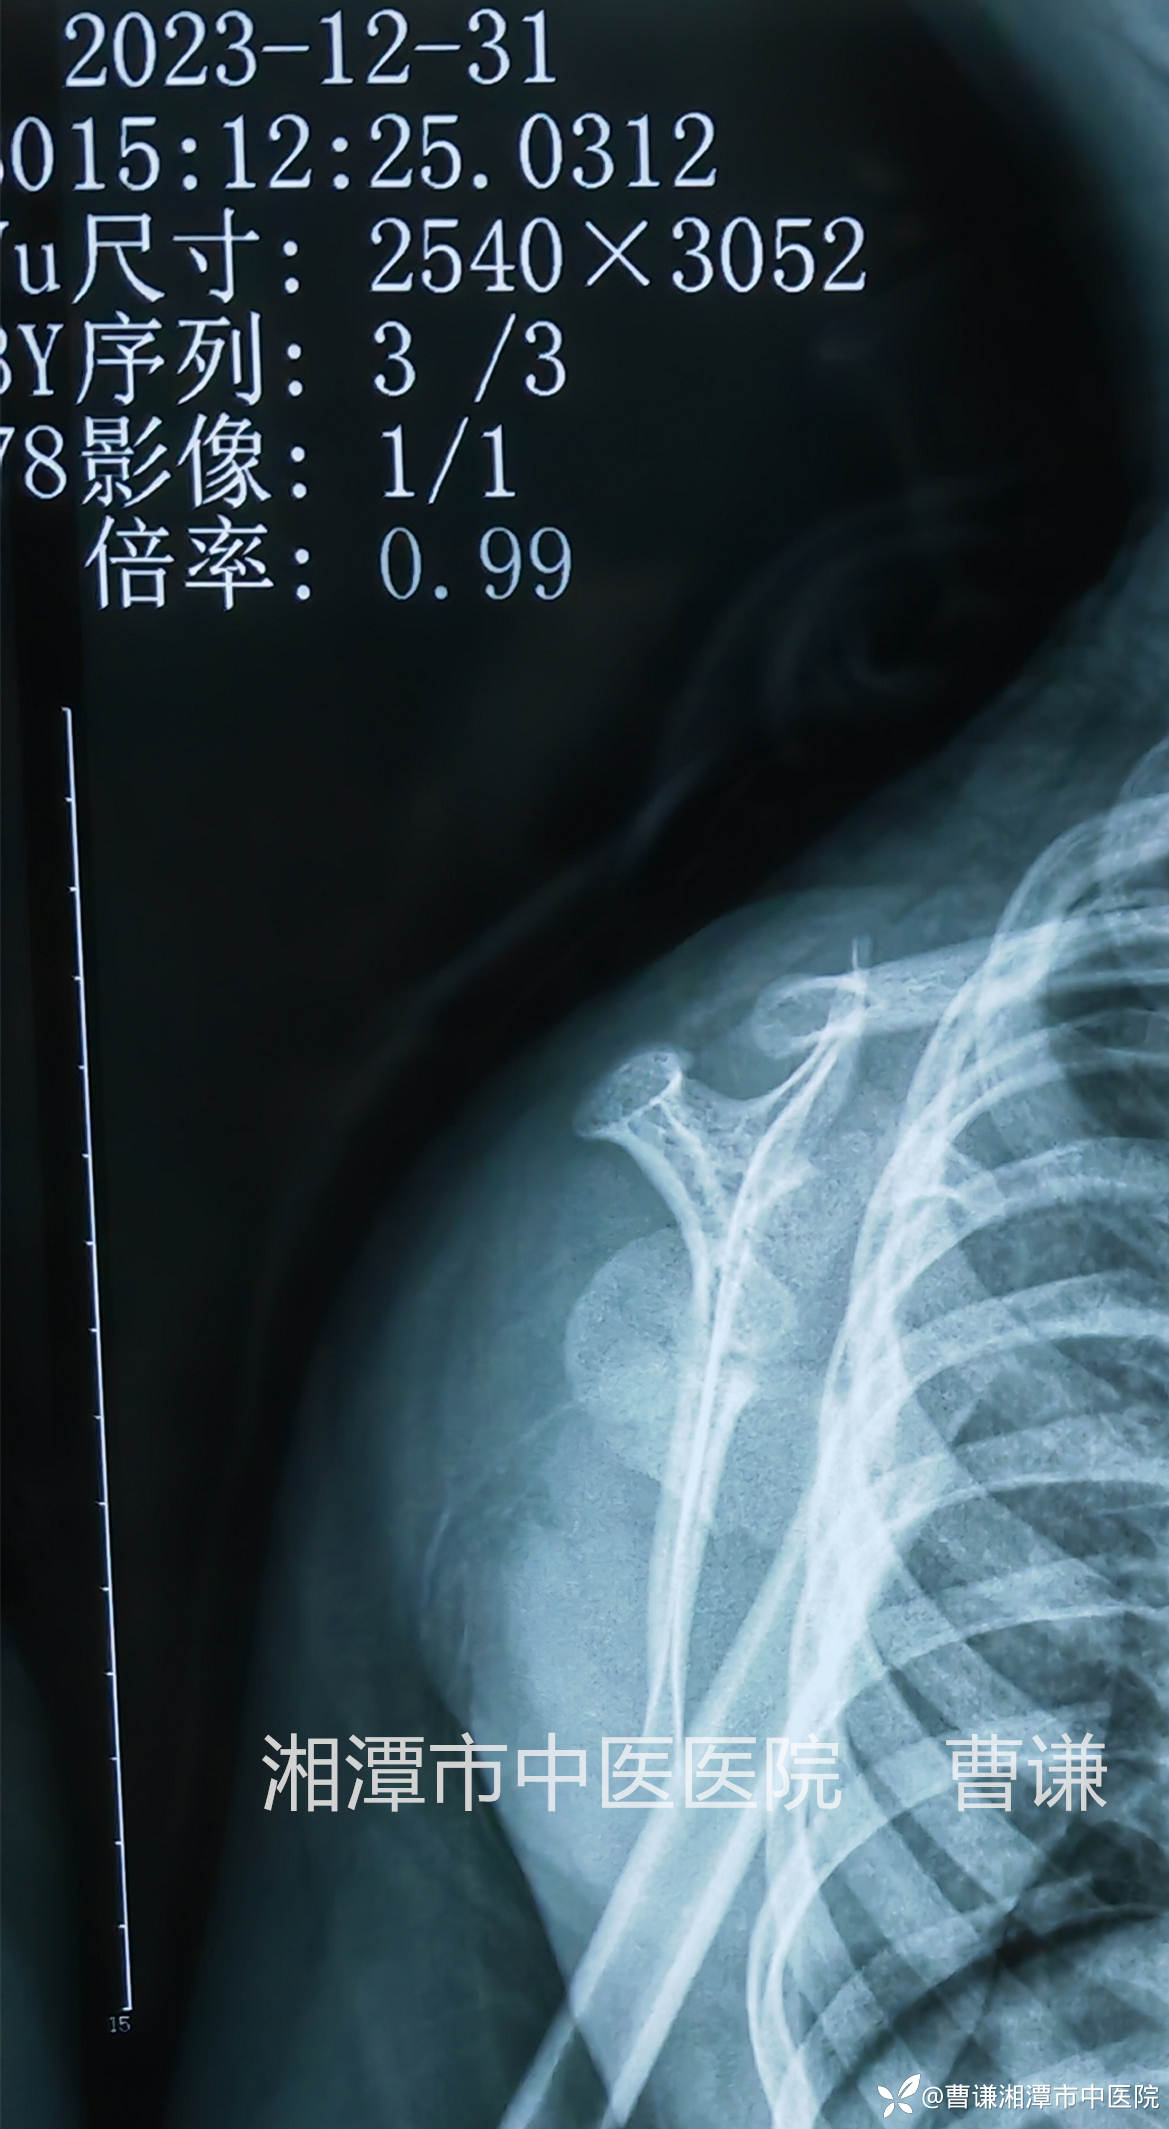

伤后9天拍片复查位置同前,既然小患者不吵不闹,天天开心的在病房走廊里瞎逛,管床大夫悬着的心也放下来了。我每天会隔着夹板压一压骨折端,问一问痛不痛,回答我的总是那个稚嫩的声音:“不痛”。然后我会带着夹板给孩子被动进行肩关节前屈、外展活动。

伤后23天拍片复查见骨折端有明显骨痂生长,予以拆除外固定,指导患者进行主动功能锻炼。

伤后23天患者肩关节上举、内旋、外旋、肘关节屈伸及前臂旋转功能均基本恢复正常。

由于干骺端血运丰富,错位明显的骨折会导致断端出血较多,肩部肿胀明显,影响复位,我们不必强求骨折解剖复位,只要使骨折端靠拢,维持稳定,等待骨折愈合塑形即可,避免暴力复位增加医源性损伤。